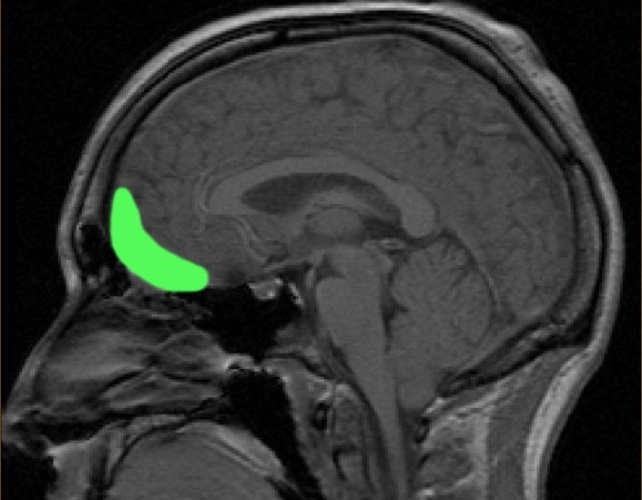

脑部核磁共振扫描图,图中绿色部分大致标示了眶额皮质的位置。( PaulWicks/公共领域/维基共享资源 )

这两种行为变化都与眶额回路的损伤有关,眶额回路参与决策,受损时可能导致缺乏人际交往能力。

如今,科学家们知道,Witzelsucht 常常与另一组称为 moria 的神经系统症状同时存在或重叠 ,而 moria 的特征是病理性眩晕。